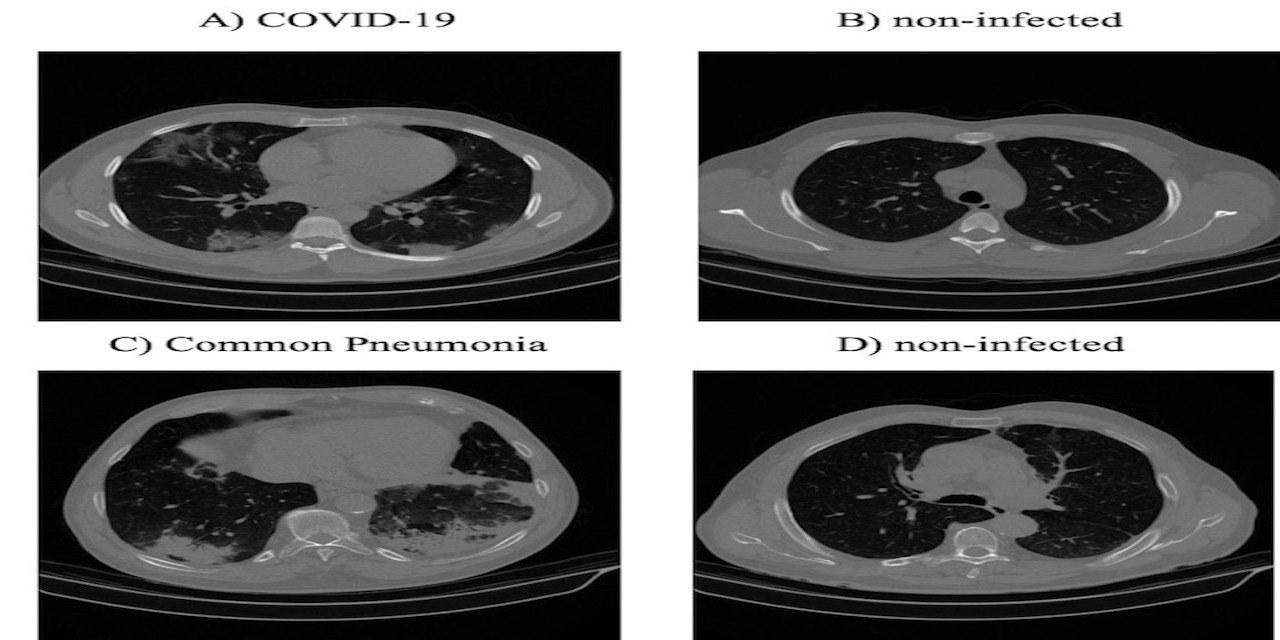

A COVID-19 CT Scan Dataset Applicable in Machine Learning and Deep Learning

Fully automated code for Covid-19 detection from CT scans from paper: https://doi.org/10.1016/j.bspc.2021.102588

Large Covid-19 CT scans dataset from the paper: https://doi.org/10.1016/j.bspc.2021.102588